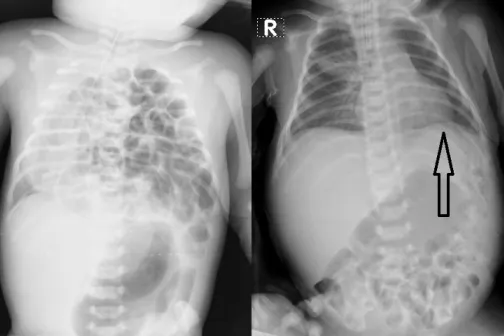

Imagine 19/10/2021 -13:54 Mama şi copilul Intervenție chirurgicală majoră efectuată în premieră, unui bebeluș nou-născut, la Institutul Mamei și Copilului